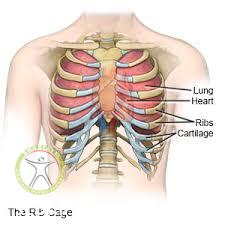

دنده ها از 12 جفت استخوان تشکیل شده اند که از جلو به استخوان جناق سینه و از قسمت پشت به ستون مهره ها متصل می باشند و در مجموع تشکیل قفسه سینه را می دهند. کار قفسه سینه این است که از ارگان های اصلی و حیاتی بدن همچون قلب و شش ها حفاظت کند.

شکستگی دنده و یا ترک خوردگی آن اکثرا در اثر ضربات سنگین که به صورت مستقیم به قفسه سینه وارد می شود مانند تصادف و همچنین سقوط از ارتفاع به وجود می آید. این شکستگی میتواند در هر یک از 12 جفت دنده اتفاق بیفتد.

در صورتیکه ضربه و آسیب وارد شده به قفسه سینه شدید باشد می تواند به ارگان های داخلی نیز آسیب جدی وارد کند.